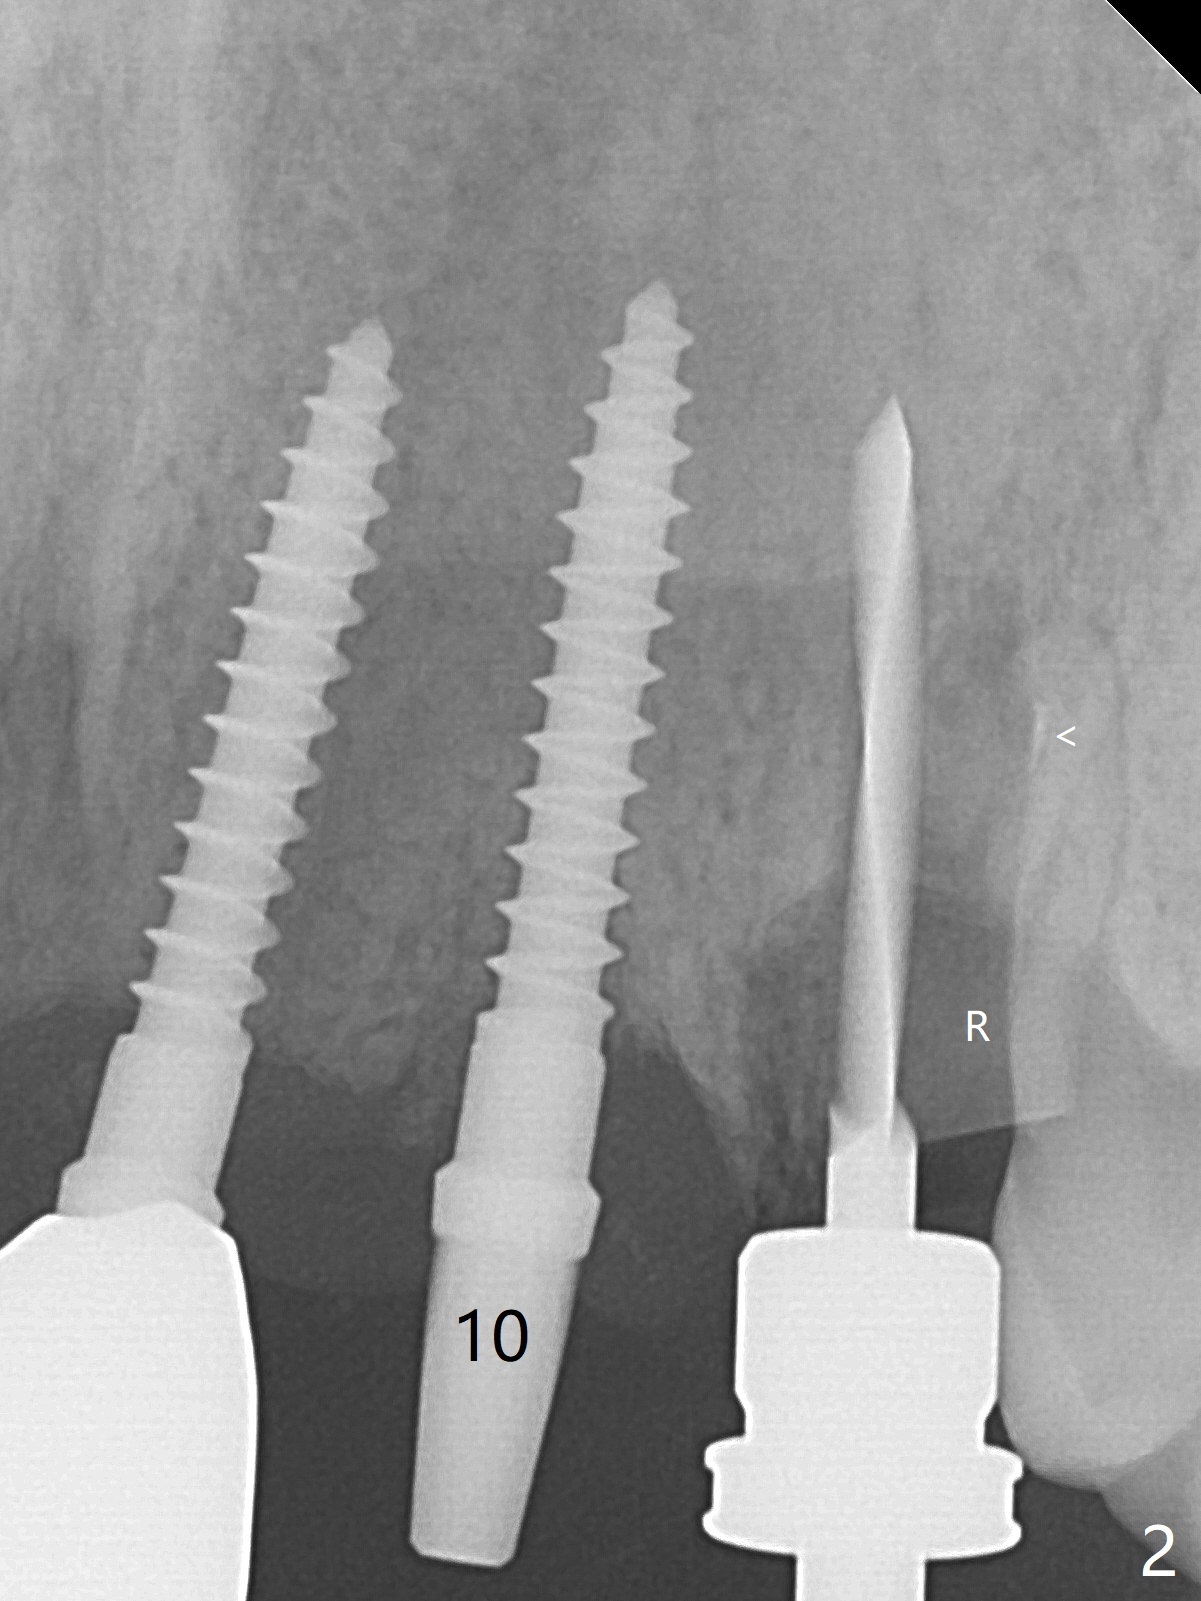

The buccal plate at #10 undergoes atrophy 9 months post immediate implant (Fig.1 *). To prevent the same post-extraction complication at #11, a technique called socket shield is going to be adopted. The buccal portion of the root (Fig.2-6 R, half-moon shaped) remains in place while a 3.5x13 mm implant is placed in the palatal portion of the socket (>50 Ncm). In fact the root is trimmed slightly subcrestal (Fig.6 C). It is assumed that there will be no or minimal bone resorption as long as the periosteum between the buccal plate and the remaining buccal root is not disturbed after tooth removal. After placement of a 4.5x15 degrees A (2mm) angled abutment and Vanilla graft (Fig.7 *), an immediate provisional is fabricated (using a central incisor crown form for #10 because of extra wide space of #11, Fig.8). There is no buccal plate atrophy at the canine 11 days postop (Fig.9). There is smooth transition from the grafted bone to the native bone 4.5 months postop (Fig.10). The buccal plate remains non-atrophic at the canine 4.5 months postop (Fig.11,12). CT taken 1 month post cementation shows that the implants at #10 and 11 are placed somewhat lingually (Fig.13,14 L (*: socket shield)). Gingival swelling is noted (Fig.15 *) with +Bleeding On Probing (^) 8 months post cementation (at the time of #21/24 impression). It appears that the socket shield (Fig.16 S) causes infection and loss of bone graft (*). The shield will be removed with an oblique accessory incision to save the papilla between #10 and 11 (Fig.17 black line). Prepare PRF for sticky bone (x1).